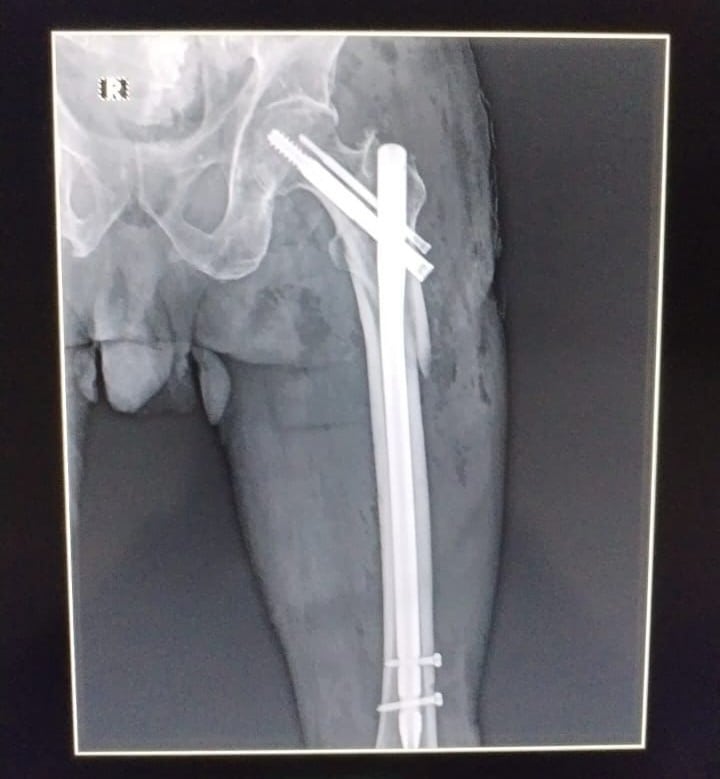

Johnnie Deng Tong, jefe de consulta externa del centro médico, afirmó que parte del equipamiento necesario para llevar a cabo este tipo de cirugías se compone de un arco en C (equipo de radiografía que permite capturar imágenes en zonas de difícil acceso sin necesidad de mover al paciente), mesa de tracción, tornillos, clavos y placas.

“La cirugía duró, aproximadamente, una hora y treinta minutos. Le colocamos un clavo intramedular que entra por el fémur y se fija con dos clavos. Para el tipo de fractura que tenía el paciente este era el procedimiento idóneo”, expresó.